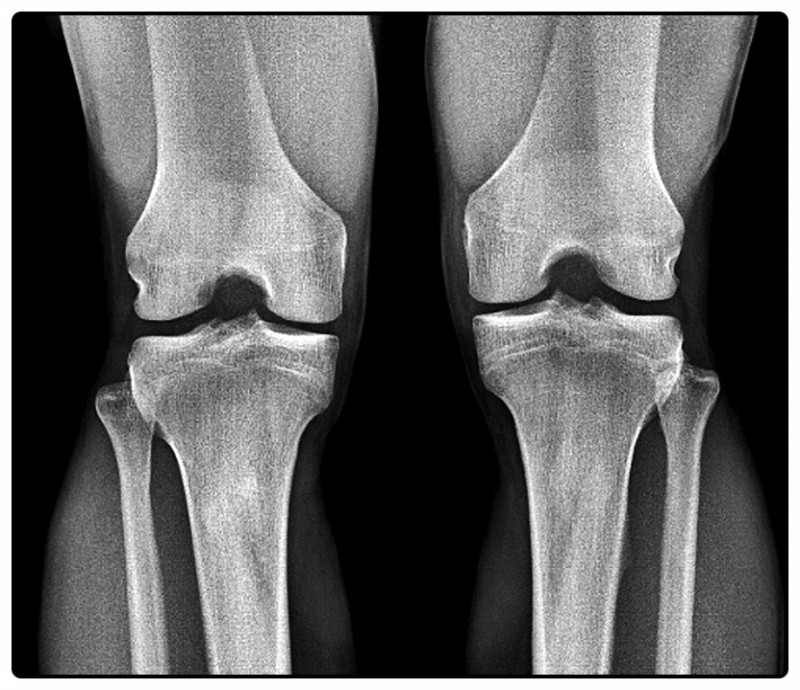

수술은 잘 끝났는데 왜 아직 아플까요?

무릎 수술은 손상된 구조를 복원해 통증의 원인을 제거하는 과정입니다.

하지만 수술로 인한 절개, 고정, 그리고 일정 기간 움직임의 제한은 근육 약화와 관절의 경직을 불러올 수 있습니다.

즉, ‘고쳐졌지만 아직 굳어 있는 상태’라고 할 수 있죠.

예를 들어, 전방십자인대(ACL) 수술 후 다리를 오랫동안 고정하면 허벅지 앞쪽 근육이 빠르게 위축됩니다.

근육의 힘이 약해지면 관절이 제자리를 잡지 못해 무릎 주변에 부담이 집중되면서 통증이 다시 생기기도 합니다.

결국 무릎 재활은, 수술로 멈췄던 관절의 기능을 다시 깨우는 과정이라고 할 수 있습니다.